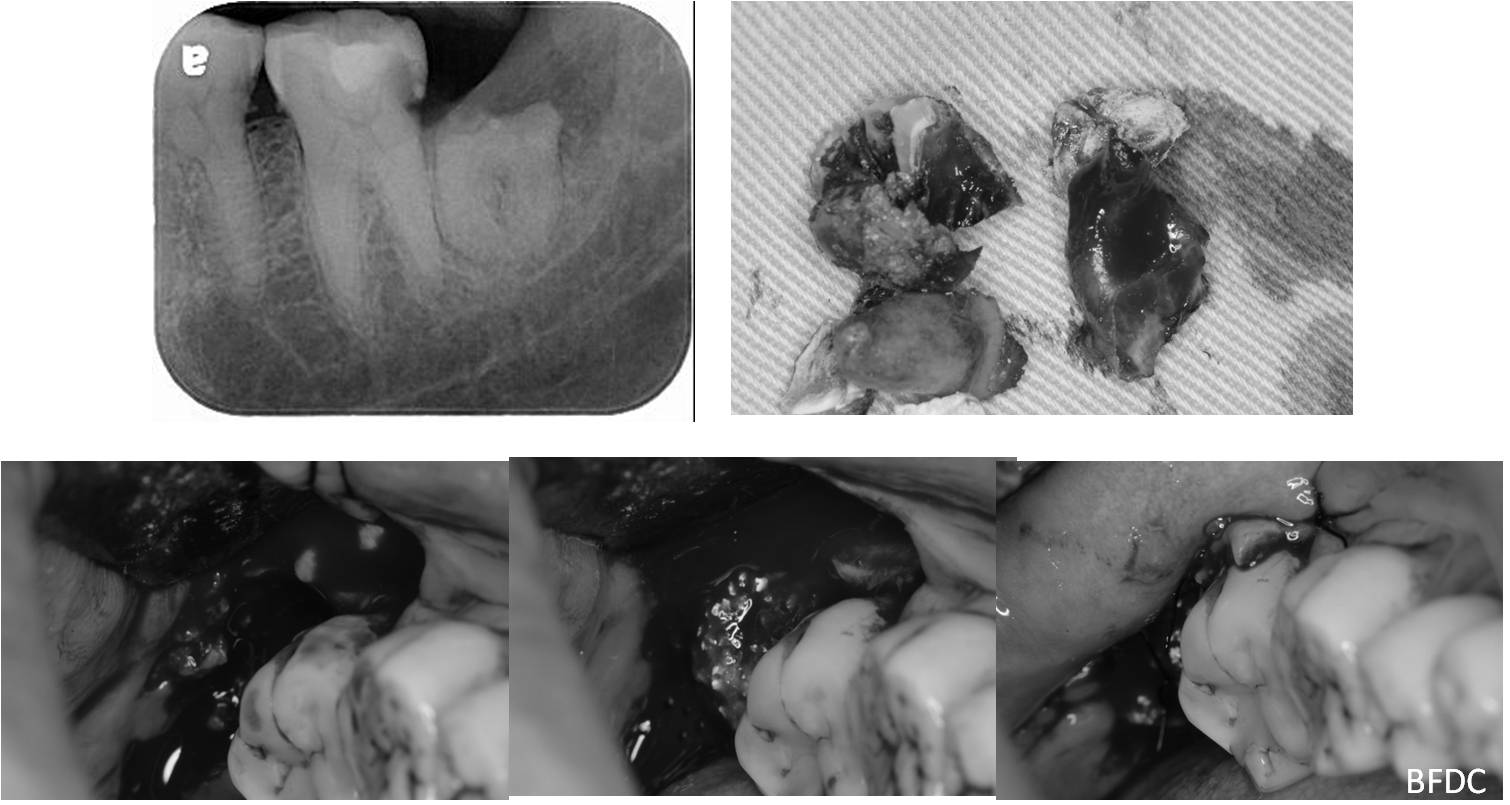

阻生齒外科手術拔除,補骨膠原

治療後,骨缺損修復

一週後,傷口逐漸癒合